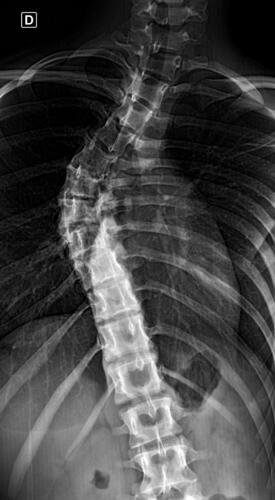

A Vá tem 13 anos e precisa urgentemente realizar uma cirurgia na coluna.Valentina foi surpreendida com o diagnóstico de escoliose hepática grave com 67 graus de desvio (desvio longitudinal da coluna), e precisa realizar com urgência a cirurgia corretiva, os exames foram realizados em Porto Alegre, mas a cirurgia está marcada para dia 13/07 em São Paulo devido a gravidade do caso, para isso a família terá que ficar residindo próximo ao hospital em São Paulo por no mínimo 30 dias para uma plena recuperação. Sabemos bem que qualquer procedimento cirúrgico é delicado, na coluna então nem se fala.Após o diagnóstico e o prognostico dessa doença a família se desfez de alguns bens (carro e moto) para cumprir os prazos dos exames e consultas, necessitando agora arrecadar o valor para a estadia da pequena Valentina e seu pós operatório (medicação, consultas e fisioterapia).

Em anexo os exames (laudo e imagens) para expressas a gravidade do caso.